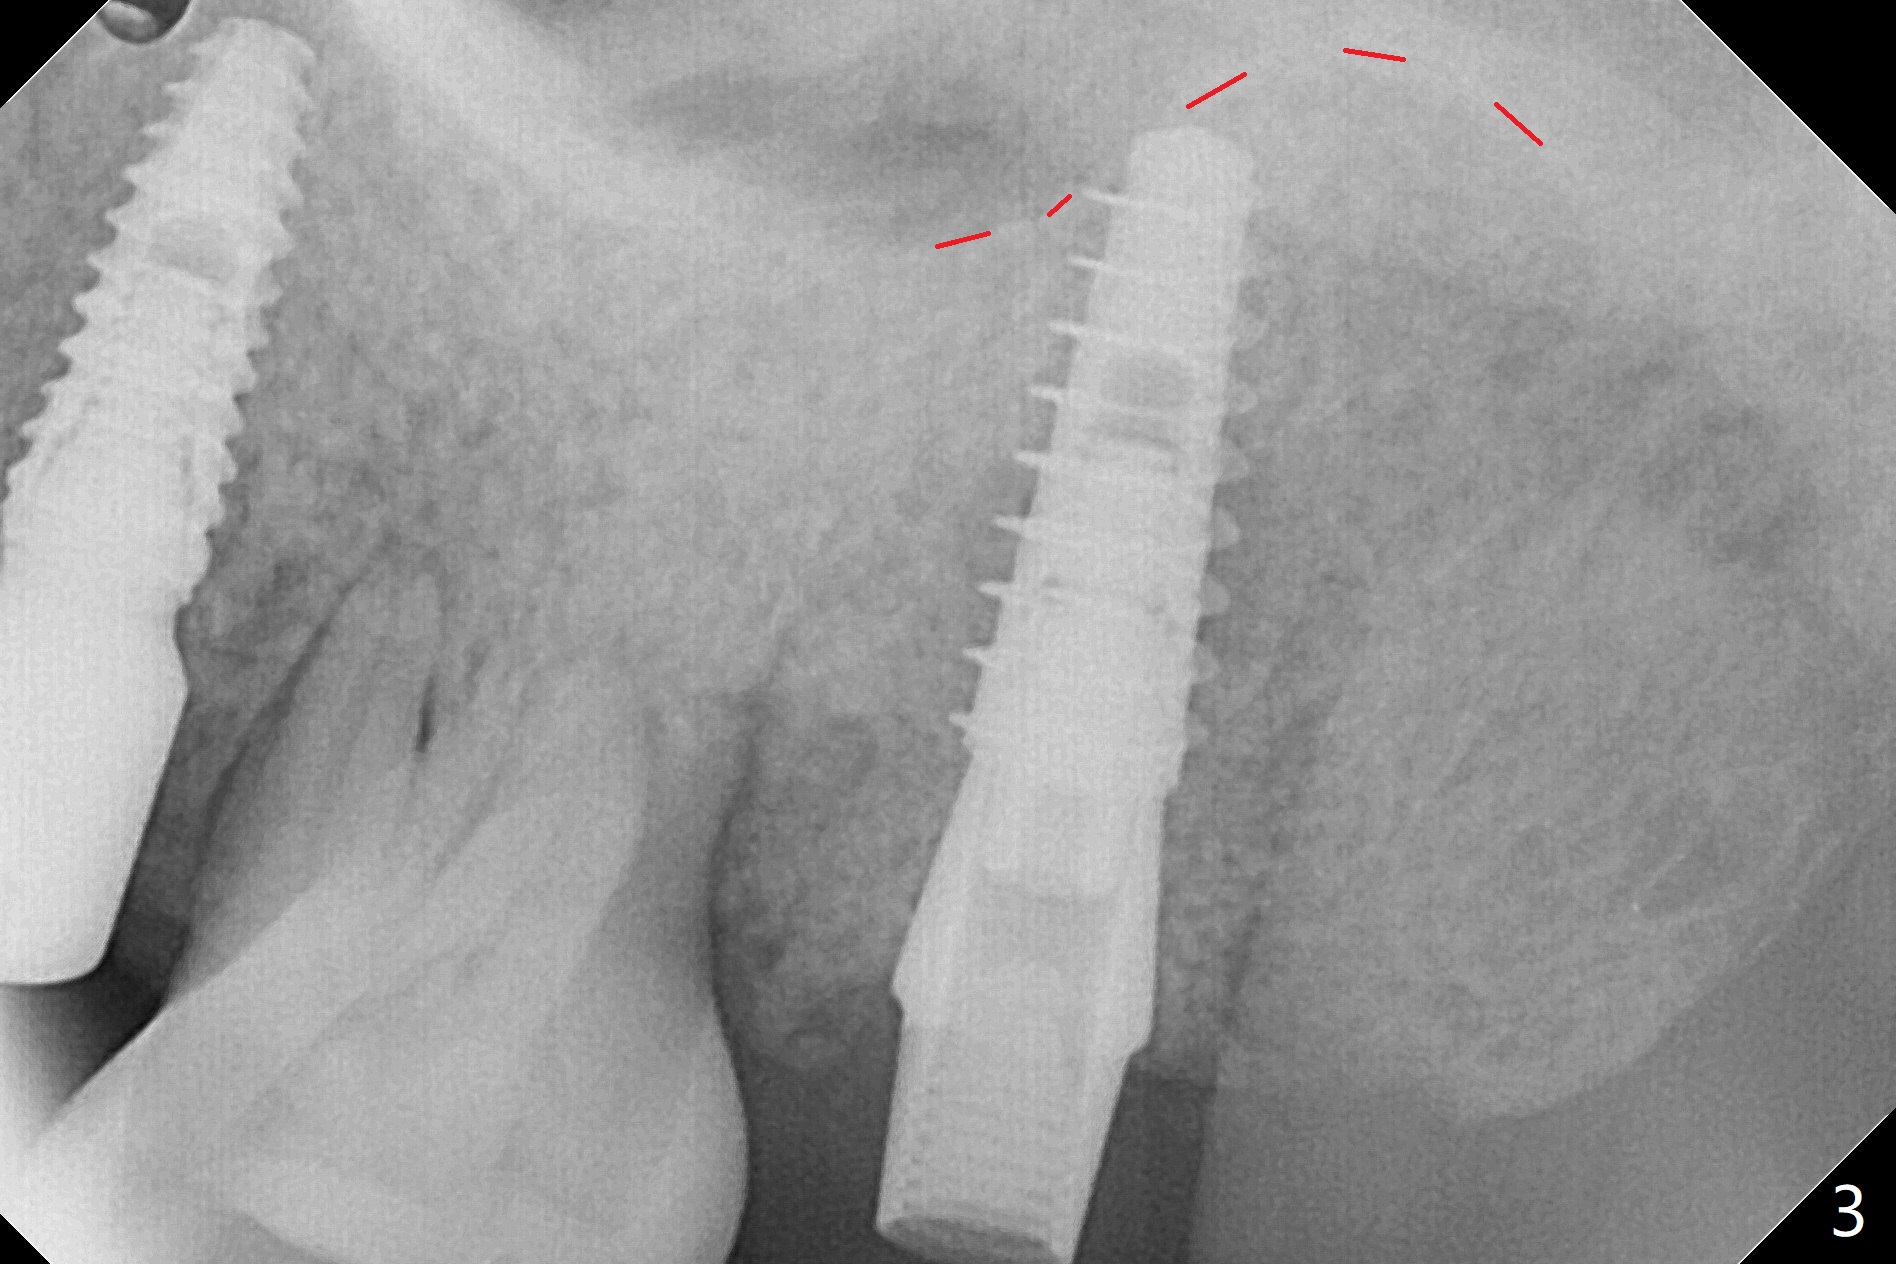

左上5延期植体扭力很高(50 Ncm,图一),而7(即刻)低(~15 Ncm),放置粘性骨粉后(图二:*),制作临时牙冠,长植体尚未穿过上颌窦底板(图三:红虚线)。